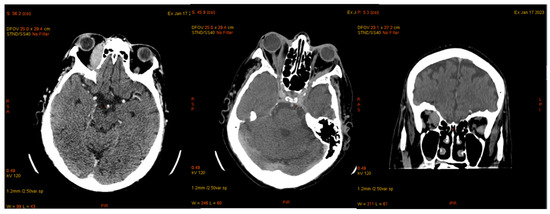

| January 2023 | second extramedullary relapse bilateral ocular left eye clinically, imaging, and biopsy demonstrated right eye demonstrated by imaging | methotrexate, asparaginase, calcium folinate radiotherapy, 30 gy/15 sessions result: imaging complete remission |

| 2 May 2023 | third emr: cardiac and colonic mass (+cns?) | nelarabine+cyclophosphamide+ etoposide |